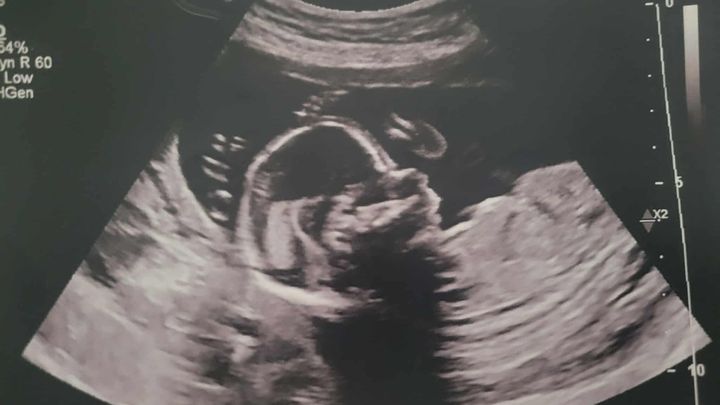

Hello, our names are Colleen and Jonathan King. We are reaching out for help with the journey of our baby girl, Oliviah. What began with the excitement of expecting another blessing from the Lord, with the silly gender mishap (as some of you know), and cute little outfits and bows, has turned to feelings of heartbrokenness, powerlessness, and shattered disbelief. Yet, through all of this, we remain hopeful, knowing that God has a hand in all of it. Following my 19-week ultrasound, we received the devastating news that Oliviah has been diagnosed with a L4 Myelomeningocele, a form of spina bifida. In Oliviah's case, the defect is low on her back, at the lumbar region, which is a good thing. She also shows the "banana and lemon signs," which is due to an elongated cerebellum, which is a sign of the Chiari II malformation, which means her brainstem is being pulled down into her spinal canal at the C2-C3 region. Her head circumference is also below percentile, caused by the Chiari II malformation.